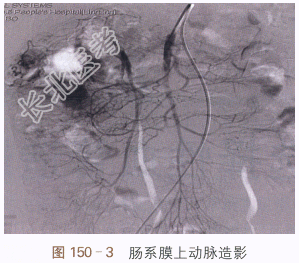

CT平扫(见图150-1)结肠肝区内可见软组织密度影,但无法与肠内容物分辨,很容易漏诊;增强CT(见图150-2)可见结肠肝区内侧管壁不规则增厚,动脉期可见多发迂曲血管显影,周围增厚的管壁轻度强化;选择性肠系膜上动脉造影(见图150-3)提示可见结肠肝区异常血管团、迂曲供血动脉及增粗的引流静脉,实质期可见圆形异常染色;内镜检查证实为肠壁息肉,表面可见出血(见图150-4)。